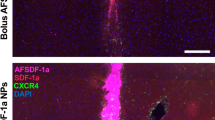

The impact of iMSC CM on angiogenesis was assessed through an endothelial tube formation assay in hCMEC/D3 cells cocultured with or without iMSCs. We found that iMSC CM caused pronounced hCMEC/D3 adherence and spreading, as well as the formation of angiogenic sprouts and short endothelial tubes (Fig. 4A, B, Supplementary Fig. 5A). CM collected from iMSCs irradiated with 5 Gy preserved the proangiogenic effect on hCMEC/D3. Additionally, iMSC CM stabilized the endothelial tube network, irrespective of the radiation status of the iMSCs, but the network started to disintegrate within 6 h of treatment (Supplementary Fig. 5B, C). Although we only observed short tubes formed by endothelial cells after CM treatment, iMSC CM treatment facilitated more complete tube network formation in the iMSC monoculture. Therefore, we next evaluated whether coculturing iMSCs and endothelial cells would enhance endothelial tube formation. Coculturing hCMEC/D3 with iMSCs indeed led to the formation of angiogenic tube meshwork by 6 h, which was better retained for up to 36 h in the presence of iMSC CM. hCMEC/D3 cells were stained green with calcein AM, irradiated at 0 Gy or 5 Gy, and cocultured with CellTracker Red-stained iMSCs in the presence of iMSC CM to determine the dynamics of tube formation. Intriguingly, a prominent meshwork of tubes started to be formed by iMSCs, and endothelial cells followed the path of the iMSC meshwork, which was augmented in the presence of iMSC CM. After 24–36 h of coculture, hCMEC/D3 cells and iMSCs aligned perfectly to one another at both nodes and angiogenic tubes in the presence of iMSC CM (Fig. 4C, Supplementary Fig. 5E, F). The amounts of analytes in the iMSC CM were not affected by IR administration (Supplementary Fig. 6).

Facilitated endothelial cell tube formation by the iMSC secretome: A Angiogenic sprout formation of hCMEC/D3 was assessed 24 h after culture on BME-precoated 96-well plates in the presence of iMSC CM. B hCMEC/D3 cells (30,000 cells/well) were irradiated with 5 Gy and cultured on BME-precoated 96-well plates for 24 h in the presence or absence of iMSC CM. Angiogenic sprouting and endothelial cell tube formation were assessed by performing calcein AM staining 24 h after iMSC CM treatment. C hCMEC/D3 cells (20,000 cells/well) were cultured on precoated 96-well plates for 24 h and irradiated with 5 Gy. The morphology was assessed 6 h after coculture with iMSCs (10,000 cells/well) with or without iMSC CM treatment. hCMEC/D3 and iMSCs were stained with calcein AM (green) and CellTracker Red, respectively. hCMEC/D3 (20,000 cells/well) and iMSCs (10,000 cells/well) were cocultured on precoated 96-well plates for 24 h. The morphology was assessed 24 h after iMSC CM treatment. RPMI medium was used as a control. The total area, perimeter and integrated density of the green and red signals in the respective images were quantified using ImageJ. The data are presented as the means ± SEMs (n = 5/group); *p < 0.05, **p < 0.01, ***p < 0.001, and ****p < 0.0001 according to one-way ANOVA or two-way ANOVA with Tukey’s test